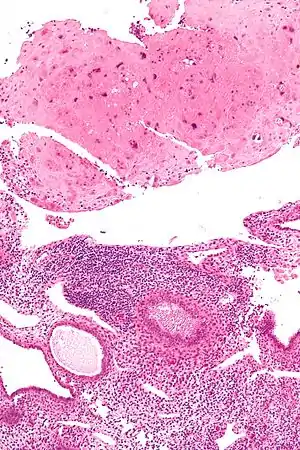

| Micrograph of a placental site nodule (top of image). H&E stain. |

Typically, they consist of pink (hyaline) material using the standard stain and contain few cells. Bizarre multinucleated cells may be present; however, there is no mitotic activity. The differential diagnosis includes (cervical) squamous cell carcinoma, gestational trophoblastic disease, and exaggerated placental site.